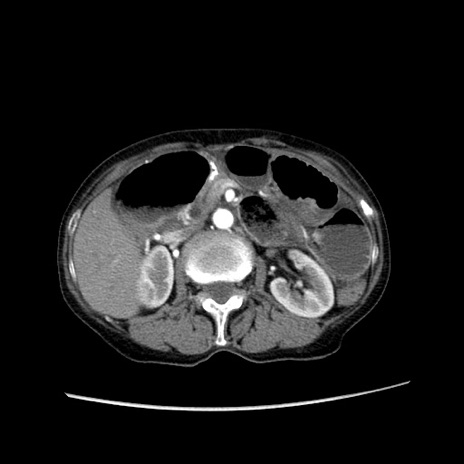

冠状断像

【症例】80歳代女性

【主訴】胸のつかえ感

【現病歴】約9時間前に食後から胸のつかえた感じあり、嘔吐あり、来院。

【既往歴】胃癌(全摘)、胆摘、虫垂炎

【身体所見】心窩部に圧痛あり、反跳痛なし。

【データ】WBC 5700、CRP 0.05